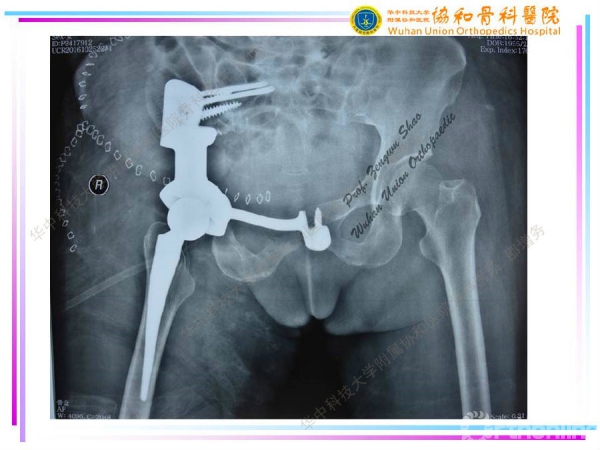

3D打印个性化半骨盆假体在骨盆肿瘤治疗中的应用

编者按--由于骨盆特殊的空间形态及周围复杂的解剖结构,骨盆肿瘤(尤其是髋臼周围肿瘤及骶髂部位肿瘤)的切除与重建一直是骨科医生面临的重大挑战之一。计算机技术、3D打印技术(3D打印骨盆三维模型、3D打印截骨导板、3D打印肿瘤假体)在骨盆肿瘤的应用,可大大提高截骨的准确性及假体的匹配度、缩短手术时间,降低假体相关并发症。2014年11月至2017年3月,华中科技大学附属协和医院骨科医院邵增务教授团队已顺利完成3D打印个性化板骨盆假体治疗骨盆肿瘤15例,近期效果满意,中远期效果有待进一步观察。